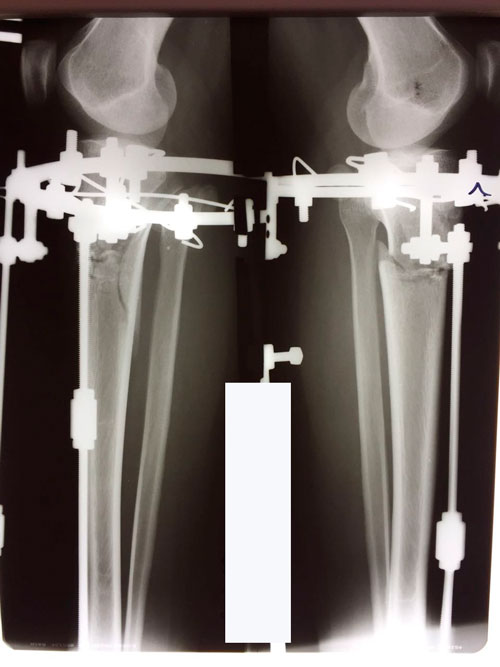

На фиксации.

Вложения

IMG-20180410-WA0050.jpg

IMG-20180410-WA0053.jpg

IMG-20180410-WA0052.jpg